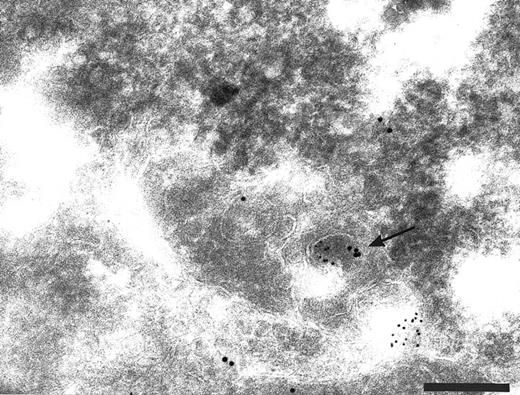

Intracellular localization of TFPI. The normal distribution of TFPI within endothelial cells, maintained in vitro, was examined on thin cryosections labeled with specific antibodies and colloidal gold probes. Label was seen associated with the cell surface and with many intracellular structures including the Golgi complex (Fig 1) and many organelles with vesicular profiles (data not shown). The surface label was irregular with noticable variation of signal intensity between cells and different parts of the same cell (data not shown). The signal appeared to concentrate over the thin cellular processes of the outer perimeter of these flat endothelial cells (Fig 1). The frequency of anti-TFPI labeling was 3.5 ± 0.5 gold particles per 10-μm length of plasma membrane (data not shown). If the anti-TFPI IgG was preadsorbed with recombinant TFPI before labeling, the frequency of TFPI labeling was 0.7 ± 0.3 gold particles per 10-μm length of plasma membrane (data not shown) and also resulted in an almost total abolition of signal over the Golgi complex (Fig 2A) and cytoplasmic vesicles (Fig 2B). Similar labeling patterns on sections through intact veins of umbilical cords were observed using αTFPI and rTFPI plus αTFPI, respectively (data not shown).

Cryosection through HUVEC labeled with anti-TFPI antibodies. Antibody binding was visualized using protein A-gold particles, some of which are indicated with arrows. This micrograph shows anti-TFPI label over the Golgi complex (G) and associated with cytoplasmic vesicles (arrowheads). Surface label (s) is concentrated on the thin cellular processes. Bar = 1 μm.

Cryosections of HUVEC showing adsorption control results. The sections were incubated with anti-TFPI diluted in medium containing rTFPI, and then with protein A-gold. (A) There is no label over the region of the Golgi complex (G) even though some nonspecific label (arrowheads) is seen over the nucleus. Bar = 0.5 μm. (B) Although the adsorption control did not completely abolish labeling (arrowheads), the amount of label is reduced and no label is observed over the many intracellular vacuoles (v) characteristic of these cells. Bar = 0.5 μm.